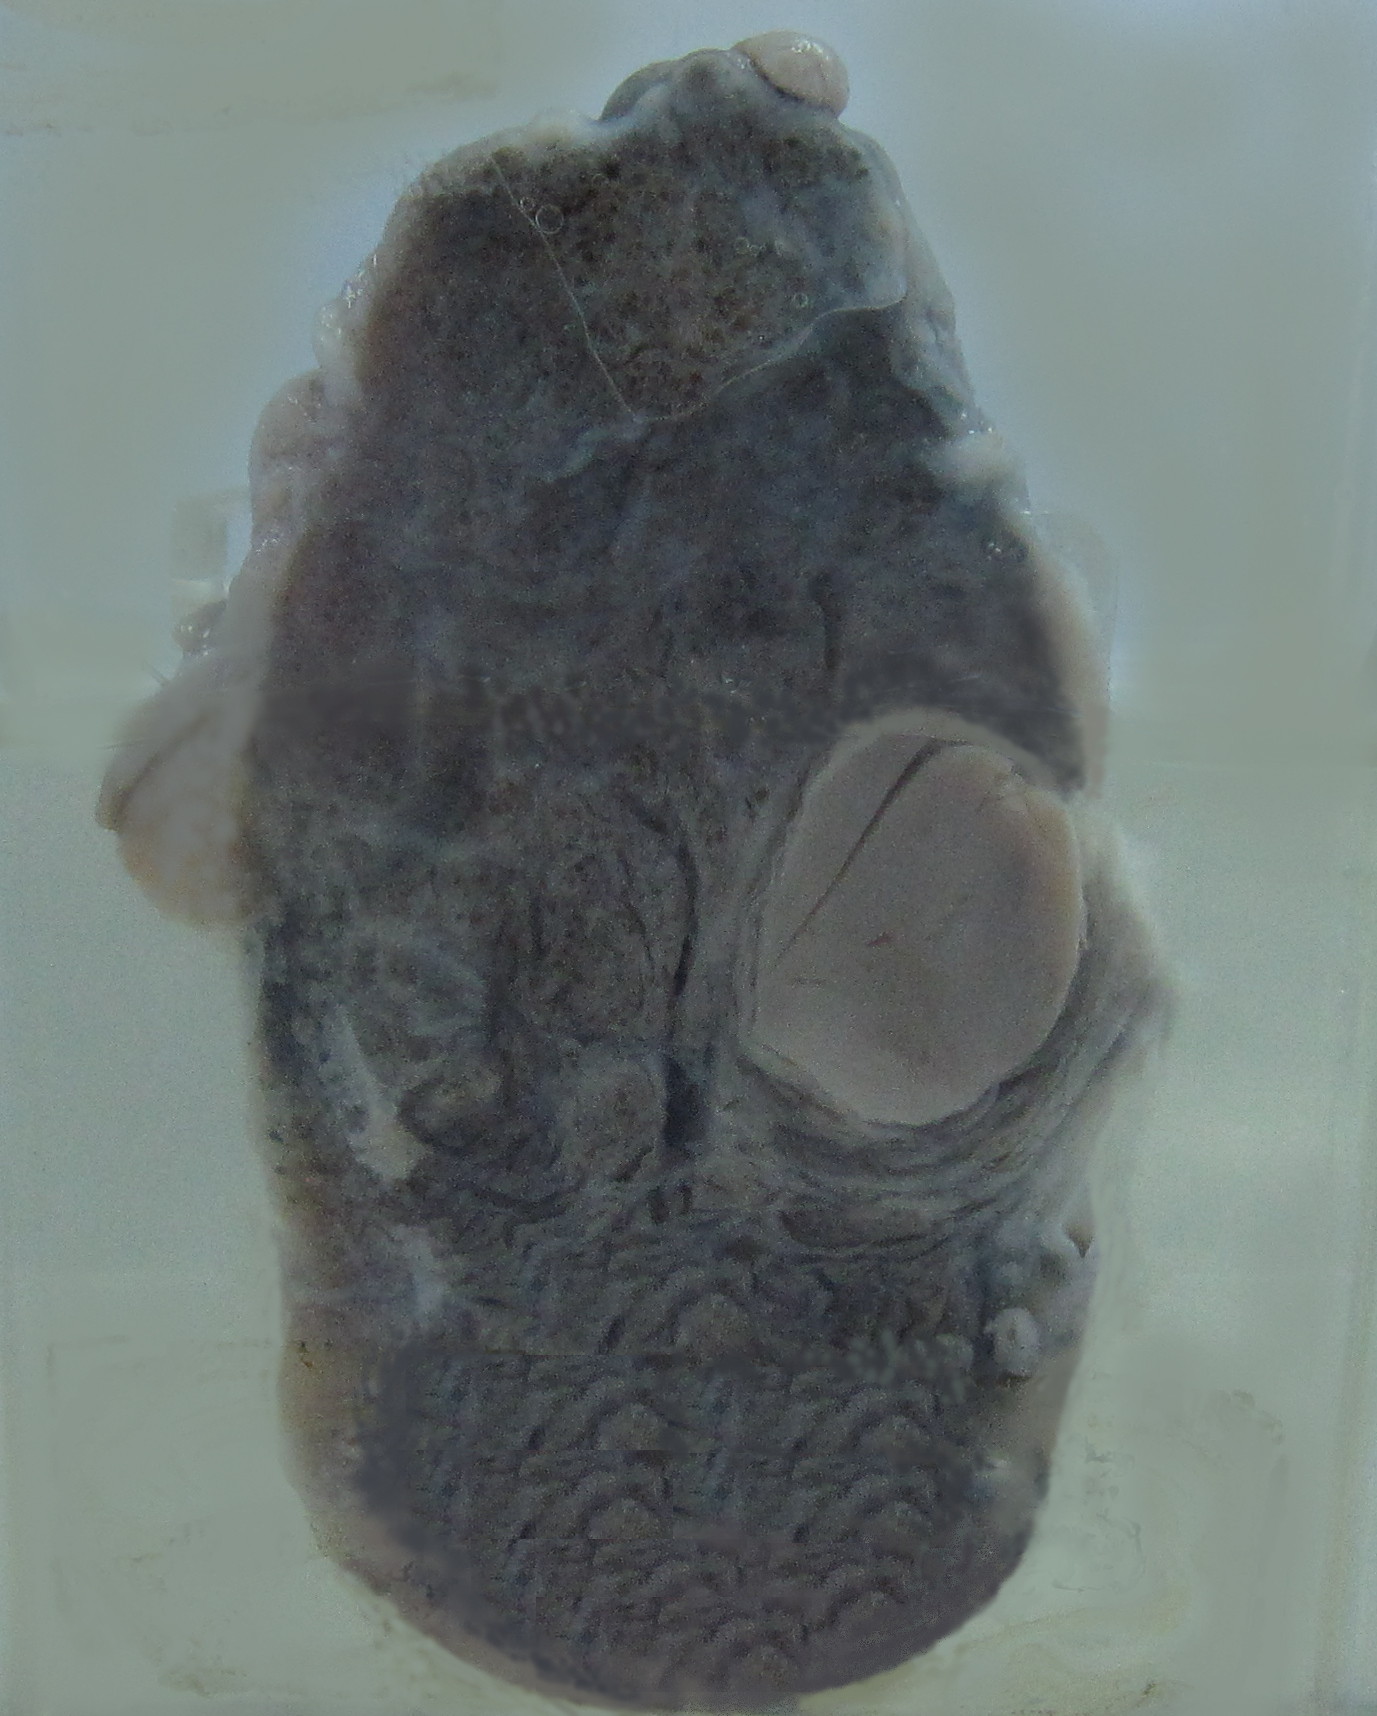

4. Adenoma of the thyroid